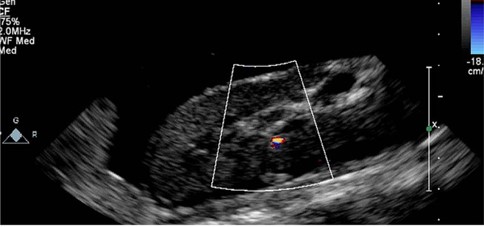

سونوگرافی